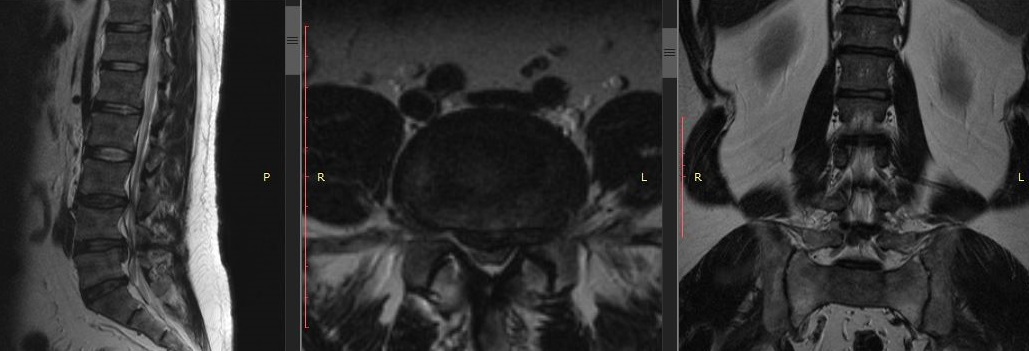

Рис - МРТ Многоуровневый стеноз

Основная причина стеноза — возрастные изменения обусловлены дистрофическими изменениями межпозвонковых дисков, связок и суставов, приводящие к истончению межпозвоночного диска и его перемещению по направлению к спинномозговому каналу, что вызывает его сдавливание. Спровоцировать подобную ситуацию способны также травмы и врожденные заболевания позвоночника.